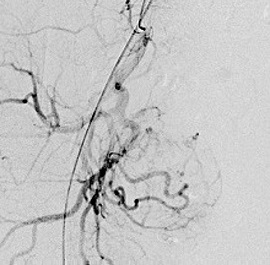

肝細胞がんに対する経カテーテル動脈化学塞栓療法の実際

大腿動脈(太ももの付け根の血管)又は上腕動脈の位置を確認し、消毒と局所麻酔を行い

ます。動脈を正確に穿刺してカテーテルを挿入し慎重に進めていきます。肝細胞がんを

栄養する血管が同定できたら、マイクロカテーテル(通常ものよりさらに細いカテーテル

)を栄養血管へ選択的に挿入し、腫瘍の近傍まで進め、そこから造影を行います。

次に肝細胞がんの径、腫瘍濃染、患者さまの全身状態、肝臓機能などを総合的に判断し

、マイクロカテーテルか治療後の造影では塞栓物質により肝細胞がんへの血流がなくな

っているので腫瘍は描出されません。

肝細胞がんを栄養する血管描出(塞栓前) 肝細胞がんを栄養する血管描出(塞栓後)

選択的動脈造影 上腸間膜動脈造影

当院では血管内治療とRFA治療を組み合わせて肝臓の機能を温存して体の負担が少なく、局所的で効果の高い治療を行っております。